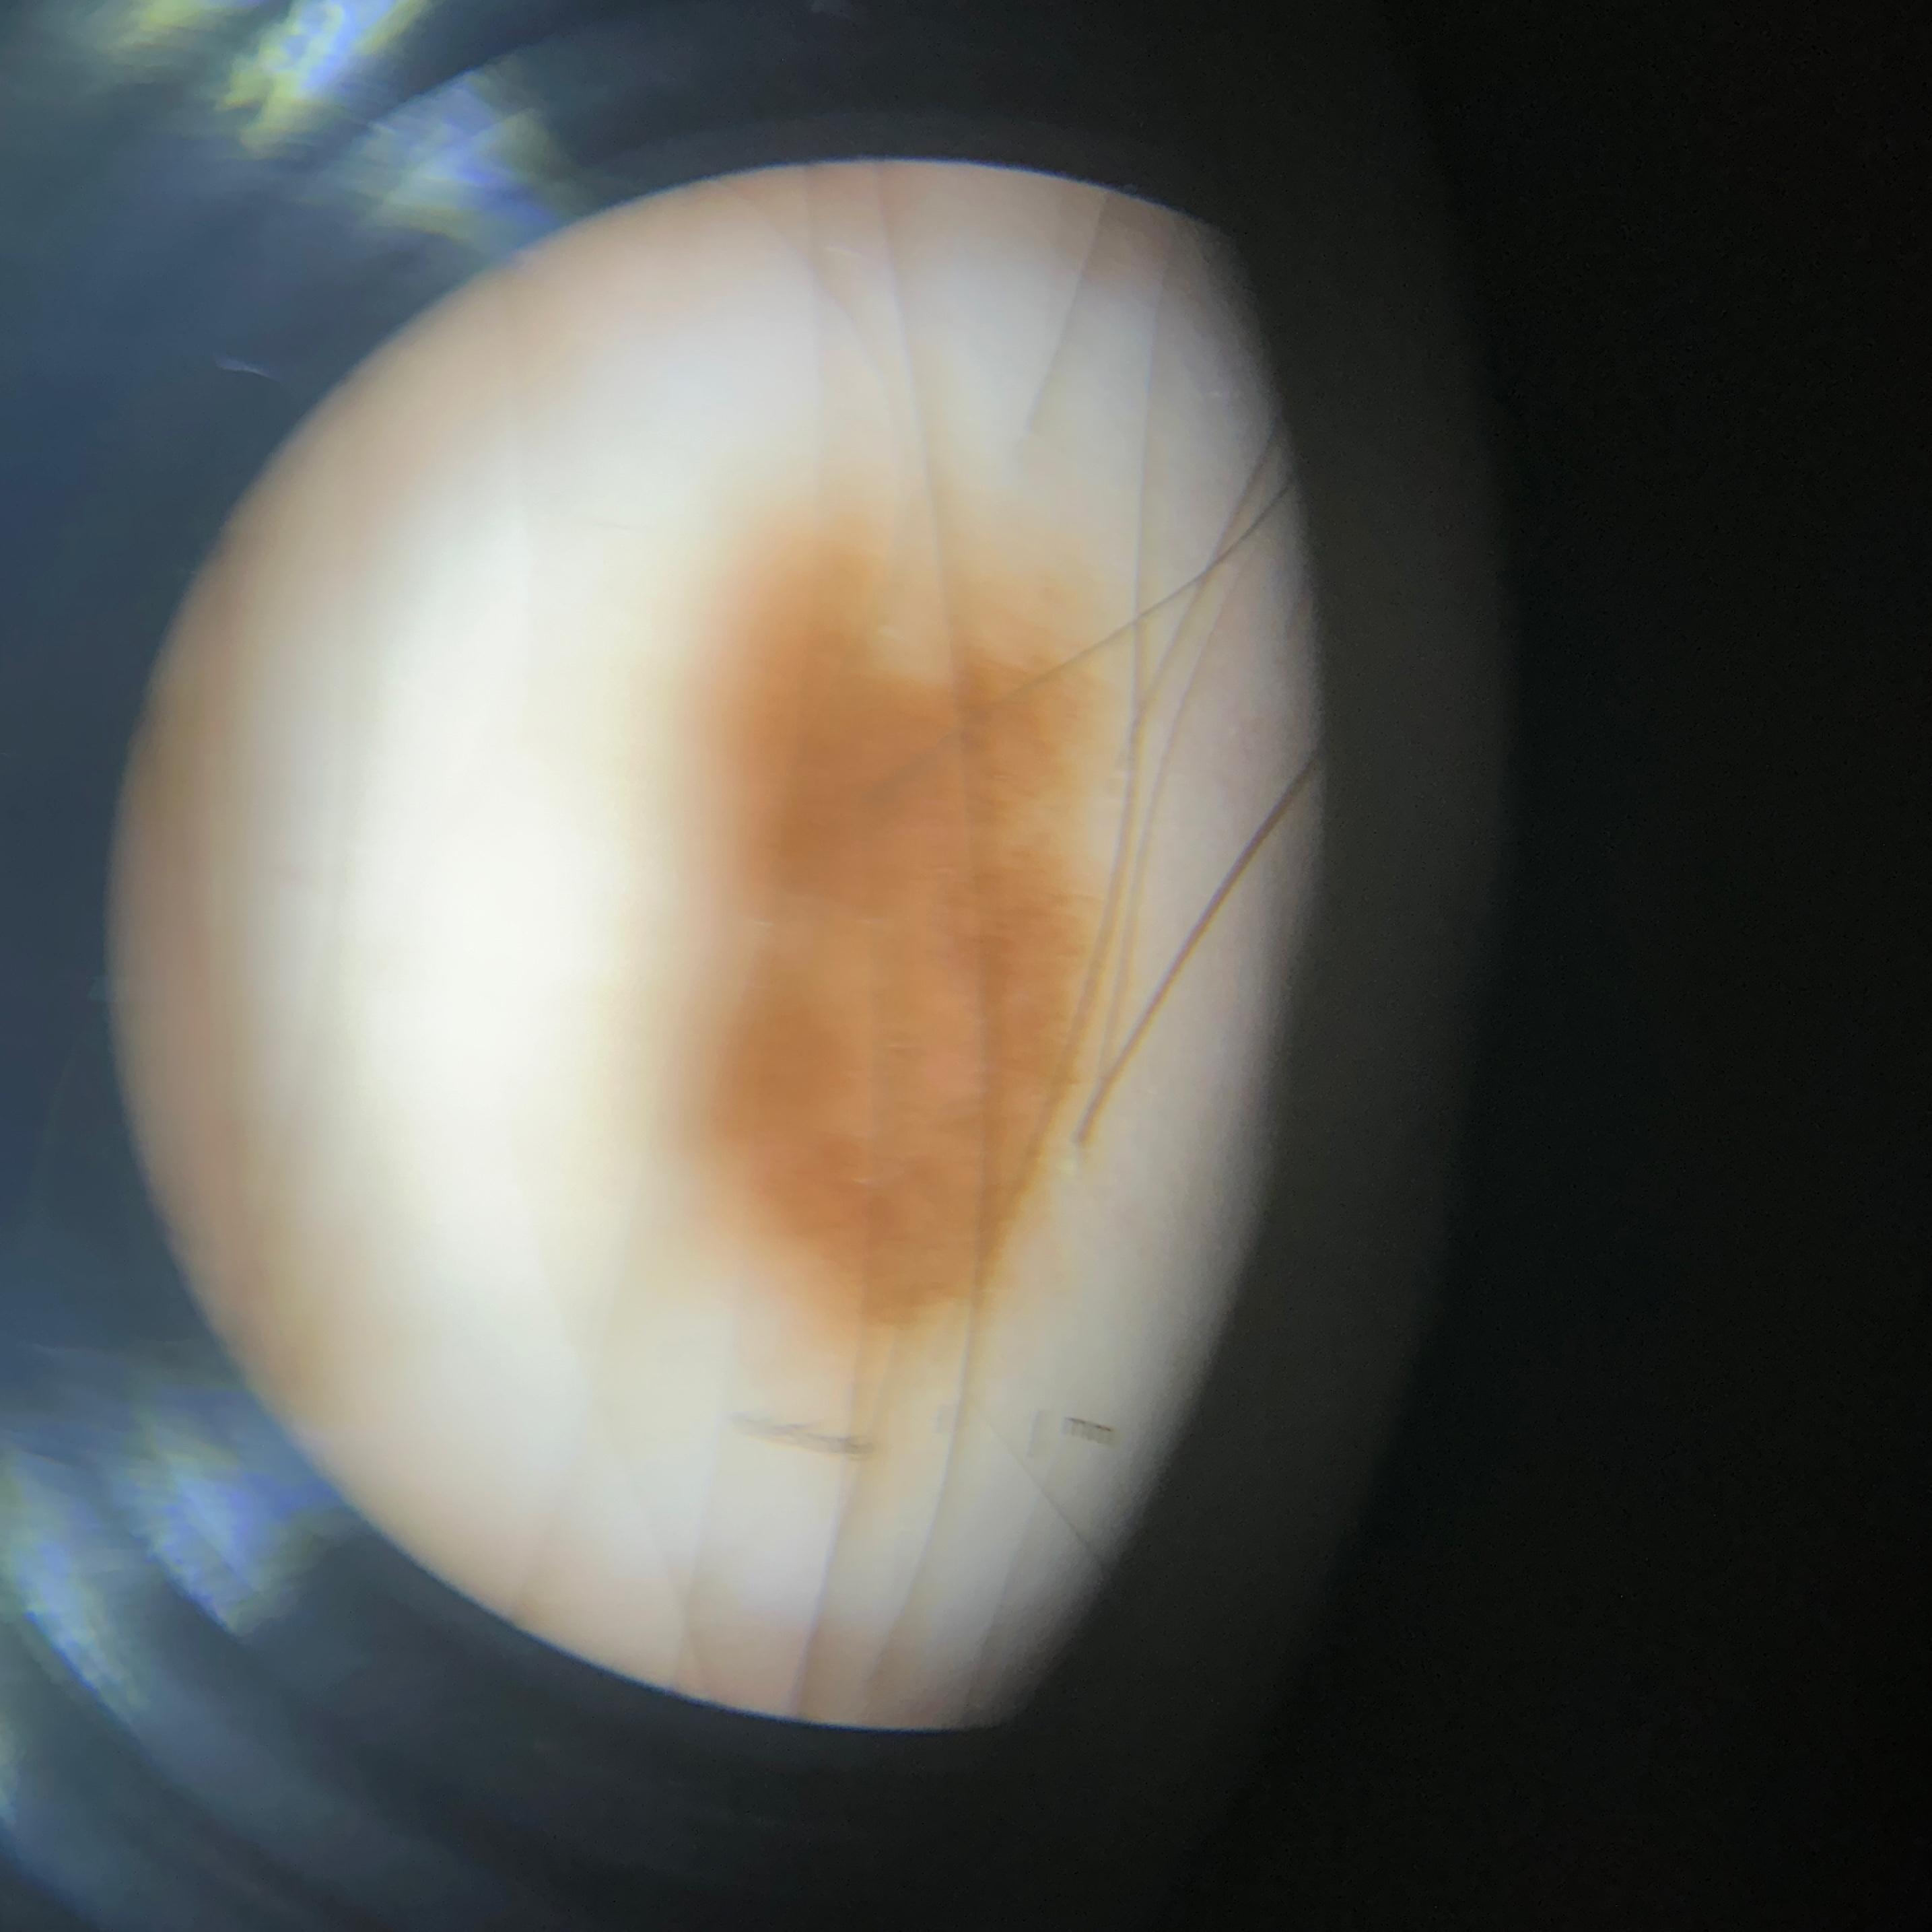

ISIC_8121870

image_type dermoscopic